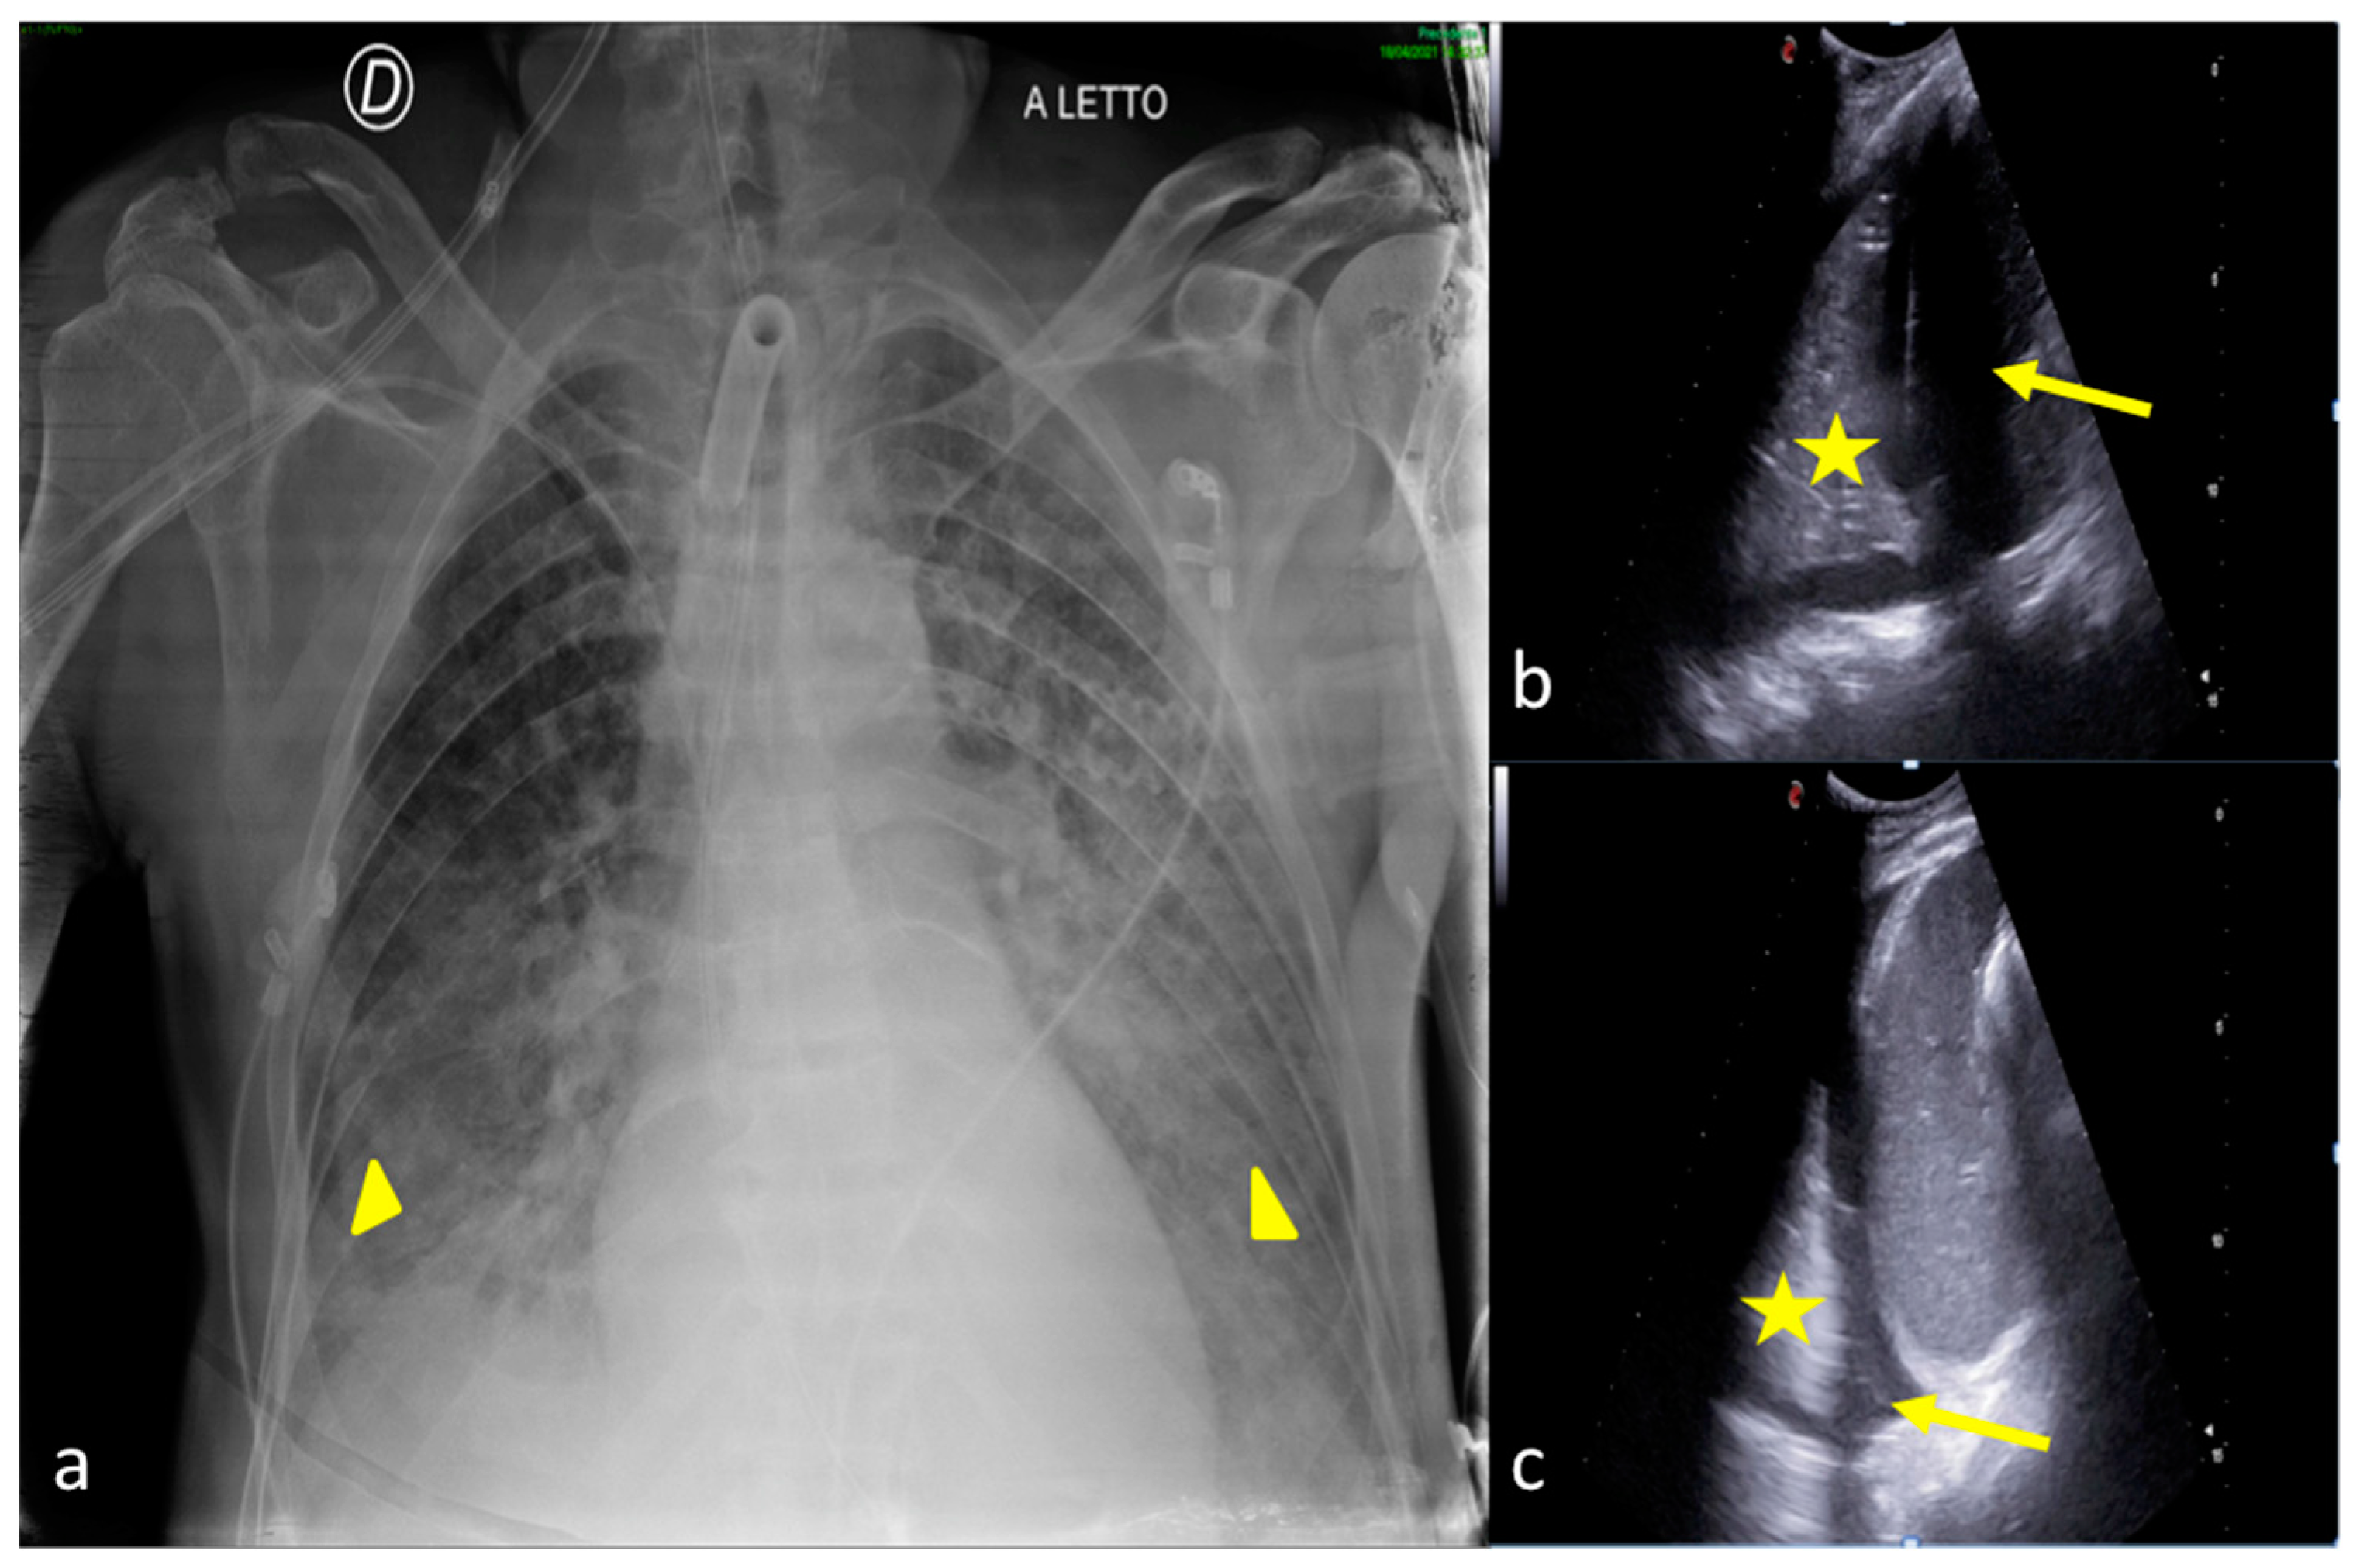

Figure 9.

A 67-year-old male patient referred to the ICU after major trauma by a fall from a height. Bedside CXR (a) and LUS (b,c). (a) The CXR showed bilateral pulmonary opacities associated with pleural effusion (a, arrowheads). (b,c) Bilateral minimal pleural fluid was also confirmed by LUS (b,c, arrows) both on the right (b) and on the left (c) sides; lung consolidation was also visible (b,c, asterisks).

Figure 10.

A 54-year-old male patient in respiratory failure. CT scan (a), CXR (b), and LUS (c). (a) The axial CT scan of the chest showed a parenchymal consolidation area with the air–fluid level in the basal segments of the right inferior pulmonary lobe suggestive of a pleural empyema (a, arrow). (b) The subsequent CXR control revealed a basal right-side decreased parenchymal transparency consistent with a persistent amount of the empyematous effusion (b, arrow). (c) LUS follow-up showed a better quantification of the residual fluid amount, with an inhomogeneous content of echogenic substance in suspension (c, arrow) and also confirmed the correct position of the surgical drainage tube (c, arrowhead).